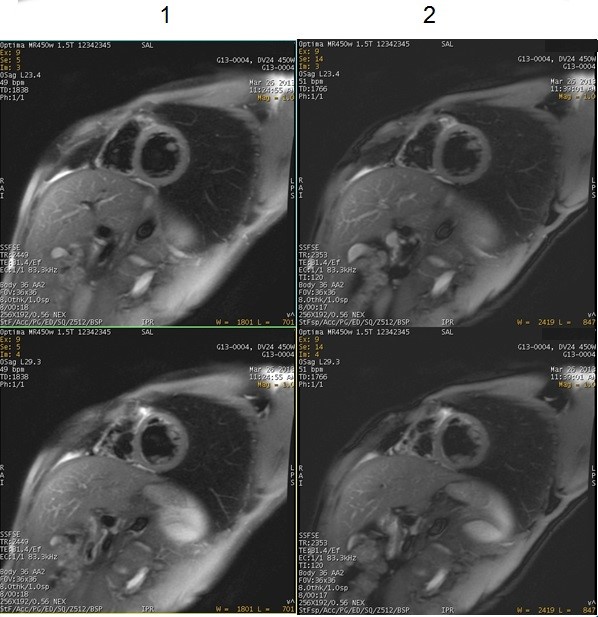

Figure 2. Good fat and blood suppression with SSFSE and fat saturation techniques

Table 1. Image legend Number Description 1 SSFSE with Blood Suppression Imaging Options and Fat SAT. 2 SSFSE with Blood Suppression Imaging Options and Chemical saturation SPECIAL. SPECIAL is the preferred fat saturation technique because it uses an ASPIR pulse, which is insensitive to B1 inhomogeneities. For more details about ASPIR, see ASPIR considerations.